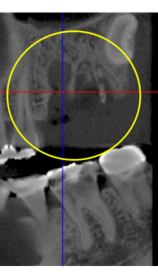

抜歯のう胞摘出

Perio Wave+Er:YAGレーザー+コールドレーザーで治療した箇所の経過です。

左から直後、1ヶ月経過時、2ヶ月経過時の画像です。

骨再生の確認をした際の動画です。

画像をクリックすると、youtubeにジャンプします。